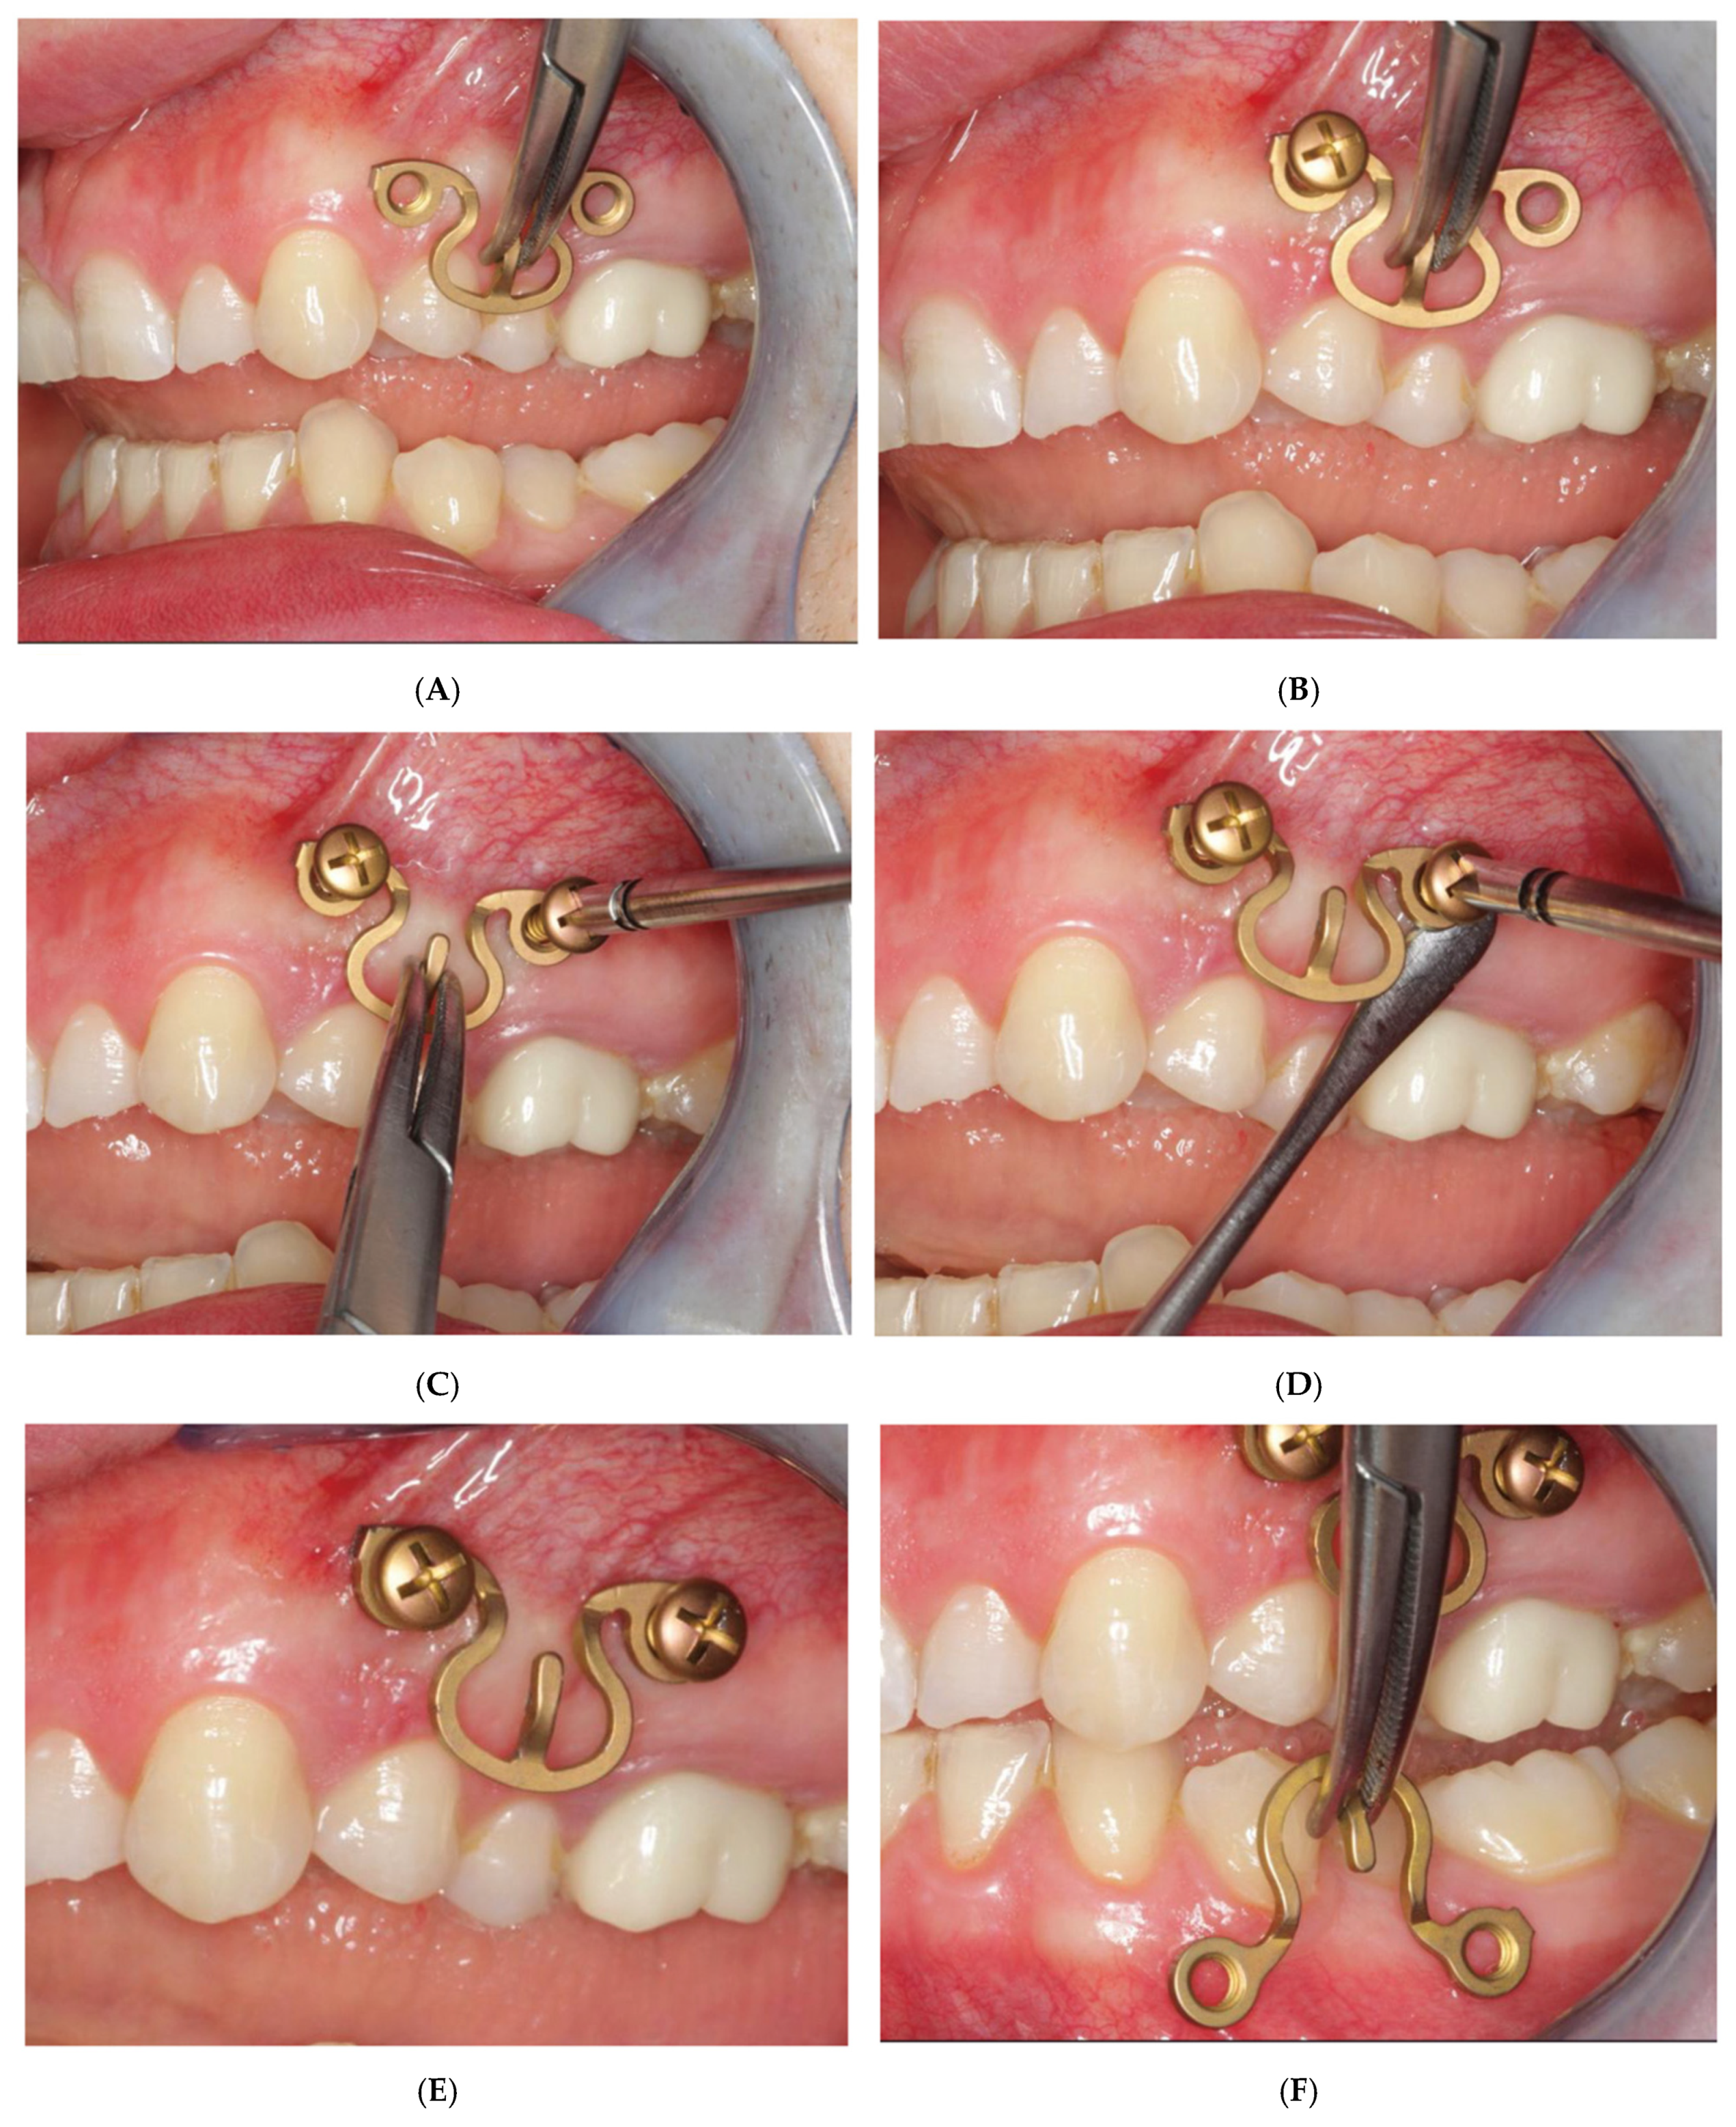

3.2. Matrix WaveTM Plate MMF System—Mode of Application

3.3. ‘In-Situ-Bending’ for Fracture Reduction